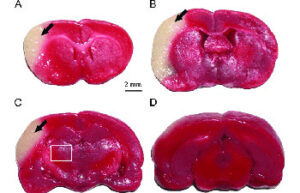

- Mice and rat brain edema test